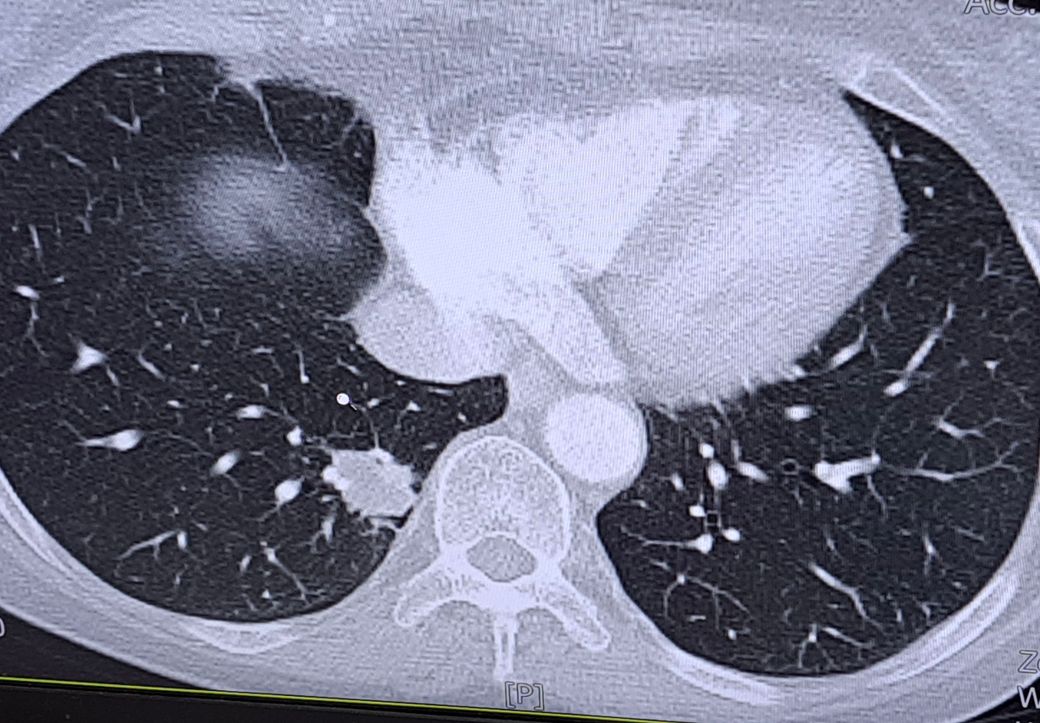

폐ct판독부탁드립니다. 폐암가능성

폐CT촬영 후 폐암으로 의심되어 조직검사를 앞두고있습니다.

조직검사까지 일정이 많이 남아 다른 분들의 소견을들어보고싶습니다.

• 1번 째 사진

• 결절의 크기가 상당히 큰 것 같습니다. margin도 뾰족뾰족하구요

악성의 가능성이 있는 것 같습니다

조직검사를 통하여 확인이 필요할 것 같습니다

• 우측 폐에 결절 소견이 관찰되고 있습니다. 악성 가능성을 염두해두고 조직검사를 해볼 필요가 있는 소견입니다. 영상을 높고 악성 여부를 판단하기는 어렵습니다.